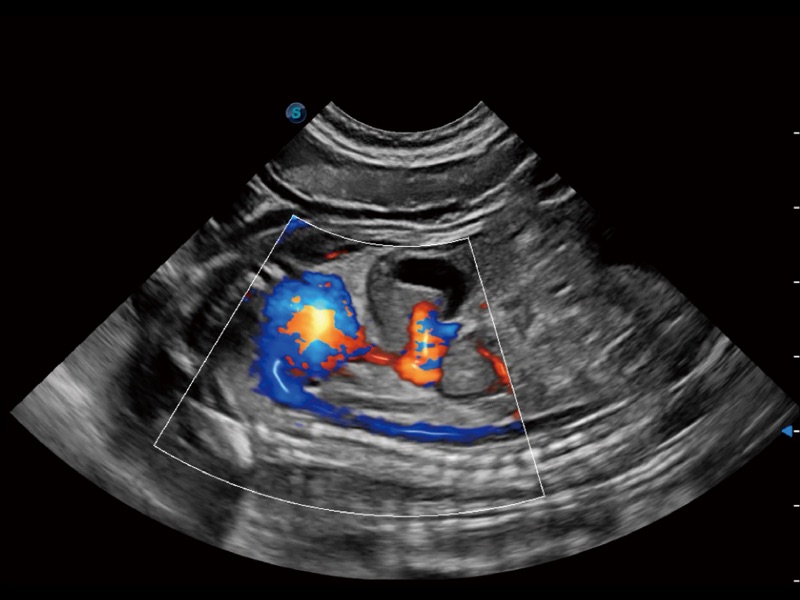

通过创新的 Matrix E自适应滤波器和超长时间域算法,极大提升超低速微细血流的检出能力,同时更精准地滤除软组织和噪声信号,为兽用医生提供以往无法通过常规血流获得的疾病诊断信息。

采用红、橙、黄、绿、青、蓝、紫这七种肉眼最为敏感的色彩,直观地显示组织内血流灌注的时间先后信息,更精准捕捉血流灌注走行细节。